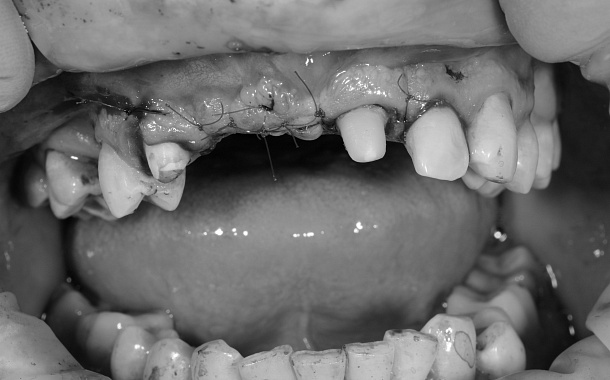

Прежде, чем приступить к удалению нескольких подвижных зубов, необходимо решить вопрос о способе их восстановления. На этапе обследования проводится тщательный анализ компьютерной томографии, планируется расстановка дентальных имплантатов в максимально выгодной ортопедической позиции, на основании которой изготавливается хирургический шаблон с запрограммированным положением имплантатов и будущая временная ортопедическая конструкция.

Обязательно выполняется клинический минимум лабораторных анализов для оценки общего состояния организма, за исключением случаев, если пациент принимает медицинские препараты по жизненным показаниям или планируется проведение удаления с анестезиологическим пособием, тогда необходимо дополнительное обследование у смежных специалистов.

Учитывая высокий риск развития септических осложнений (негативного влияния бактерий пародонтальных карманов и их токсинов на жизненно-важные органы), перед удаление зубов обязательно назначается профилактический прием антибактериальных препаратов.

Каждый клинический случай уникален и требует индивидуального подхода, чтобы в кратчайшие сроки завершить лечение.

На сегодняшний день отработаны общепринятые методики восстановления зубного ряда на 4-х и 6-и имплантатах с немедленной нагрузкой временными ортопедическими конструкциями и их последующей заменой через 4-6 месяцев на постоянные.

Однако, не стоит забывать о том, что для подобных реконструктивных операций существует строго определенное условие, а именно достижение первичной стабильности установленных имплантатов, способных выдержать немедленную нагрузку, зависящую напрямую от объема и качества костной ткани в области планируемого удаления зубов.

Как происходит удаление нескольких зубов с немедленным восстановлением зубного ряда?

1. Анестезия или погружение в «сон».

2. Атравматичное удаление подвижных зубов с минимальной травмой костных стенок лунок корней.

3. Антисептическая обработка костной раны, кюретаж грануляций, то есть удаление из лунки тканей, поддерживающих воспалительный процесс и препятствующих правильному заживлению лунки.

4. Наложение и фиксация хирургического шаблона, установка дентальных имплантатов в запрограммированном положении, контроль первичной стабильности имплантатов.

5. Заполнение лунок и дефектов альвеолярного отростка костно-пластическим материалом BioOss, закрытие зоны подсадки костной ткани мембраной богатой тромбоцитами - APRF.

6. Ушивание раны.

7. Фиксация и коррекция временной ортопедической конструкции (временных протезов).

8. Замена временных ортопедических конструкций на постоянные через 4-6 месяцев.